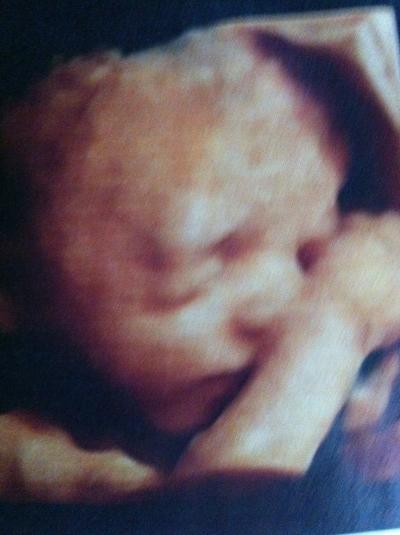

Hallo Mädels, ich bin jeden Tag bei euch nur fehlt mir grad im Alltagswahnsinn die Zeit zum schreiben. Aber heute hatte ich ein soo tolles Erlebnis. Letzte Woche bei der Vorsorge sagte mein FA das die Masse der Oberschenkel und des Kopfes passen würden aber die des Bäuchleins um 3 WOchen zurück lägen. Daraufhin bin ich heute auf eigene Faust zu meinem Prenataldignostiker der auch der Meinung das sie hinterher hinkt aber er meinte nur 1-1,5 Wochen und das sie eben kein Riese wird. Was nach wie vor ist das ich in der linken uterina einen leichten WIderstand habe der das Wachstum beeinflussen kann. Daraufhin bin ich zu meinem Gyn und habe ihn gebeten doch jetzt von 4 Wochen Abständen auf 2 Wochen Abstände zu gehen einfach weil ich Angst habe und er stimmte zu. Was aber ganz toll war heute ist , ich hatte ja diese Bauchdeckenstraffung und noch nie , bei keinem meiner 8 Kids habe ich ein 3 D Bild bekommen . Erst gab es das nicht und dann hatte ich die Narben. Heute hat bevor der Doc kam erst die Schwester vermessen und auf einmal schaltet die auf 3 D. Ich war zu Tränen gerührt. Und dann kam nochmal ein ganz anderes Bild wo sie mir erklärte das das der allerneuste 3 D wäre den sie noch nicht probiert hätte und ich wäre ihr Versuchtsobjekt. Wahnsinnsfotos.......... ich könnte die kleine Maus jetzt schon knutschen Ich hänge sie euch mal an....so ein tolles Erlebnis....für mich...denn Mausi hatte einmal einen Arm, dann den Zweiten Arm und dann beide Arme vorm Gesicht. Dann hat sie den Bauch eingezogen beim Messen (typisch Weib) und dann hat sie uns die Zunge rausgestreckt aber das wollte sie net als Photo drucken weil sie meinte da bekämen die Geschwister ja Angst. Sorry jetzt isses so lang, aber dafür schreib ich ja nicht so oft :-) Ich wünsch euch allen einen tollen Abend Drücklerle Nicole mit den 8 Kids und Laylani inside

und ein Grinsebildchen